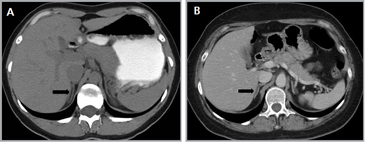

Las masas suprarrenales son un hallazgo frecuente en la población general, con una prevalencia que varía entre un 1a un 8,7% en grandes series de autopsias. Los incidentalomas se describen en aproximadamente un 4-6% de la población (Figura 4 a y b), y su prevalencia aumenta con la edad, siendo de 0,2% en pacientes entre 20 a 29 años, y de 7 a 10% en pacientes de mayor edad4. Se observan también con mayor frecuencia en pacientes obesos y diabéticos, especialmente de sexo femenino.

A

BLa mayoría de estas lesiones, hasta un 98% de los casos, resultan benignas en el contexto de pacientes sin historia conocida de neoplasia maligna. De modo contrario, si existe el antecedente de una neoplasia maligna extraadrenal la probabilidad de que un incidentaloma suprarrenal corresponda a una localización secundaria aumenta significativamente. Hasta un 27% de los pacientes oncológicos tienen metástasis suprarrenales microscópicas y aproximadamente un 50% de las lesiones suprarrenales pesquisadas de manera incidental en este tipo de pacientes representan enfermedad metastásica4.